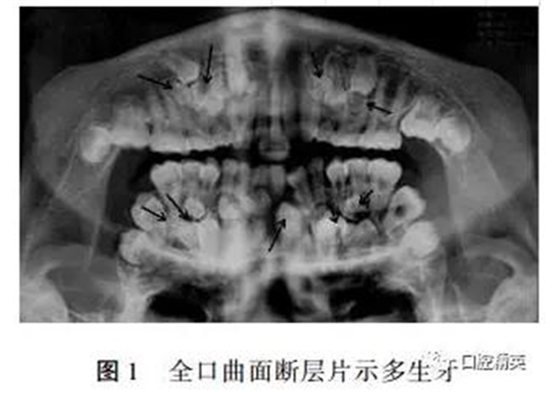

??茩z查:面部對稱,張口度未見異常,混合牙列:51、52、53、55、61、63、65、74、75、83、84、85未替換,14、16、22、24、26、31、32、33、36、41、42、46已萌出,咬合關(guān)系可。全口曲面斷層片示(見圖1):右側(cè)上頜前牙區(qū)及磨牙區(qū)可見5顆多生牙及未萌出的11、12、13、15,左側(cè)上頜前牙及前磨牙區(qū)可見3顆多生牙及未萌出的21、23、25,左側(cè)下頜前磨牙區(qū)可見2顆多生牙及未萌出的34、35,右下前磨牙及尖牙區(qū)可見4顆多生牙及未萌出的43、44、45。其中大多數(shù)多生牙牙冠形態(tài)近似前磨牙,部分牙齒牙根尚未形成,17、18、27、28、37、38、47、48牙胚形態(tài)基本正常。

診斷:多發(fā)性多生牙?;颊呒议L要求轉(zhuǎn)院,遂出院。